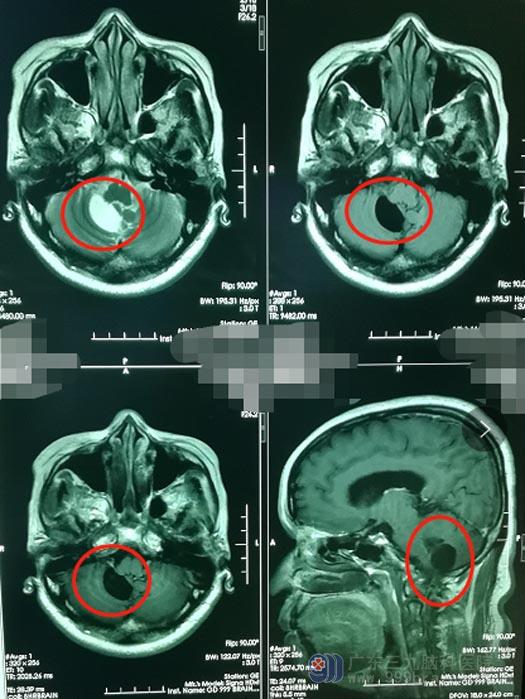

最近一周时间,黄阿姨的头痛越来越严重,到了难以忍受的地步,便去当地医院做了头颅CT检查,影像结果提示:“小脑占位”。全家人当时就呆了,只隐约记得医生说需要开颅将肿瘤切了,想到要做这么大的手术,都甚为担忧,通过四处打听,他们选择了广东三九脑科医院神经外五科。

医院副院长、神经外五科主任鲁明告诉黄阿姨,小脑肿瘤初期症状不明显而且没有什么特异性,所以容易忽视;经常头痛是最常见的,早期症状常常发生在清晨四五点钟往往是在熟睡中被痛醒,起床轻度活动之后头痛会逐渐的缓解和消失,有时伴有恶心、呕吐,其原因都是颅内压增高所致,及时手术切除是目前最好的治疗方法。家属知情同意后,黄阿姨接受了“全麻下右侧小脑占位病变切除术”。

▲手术前